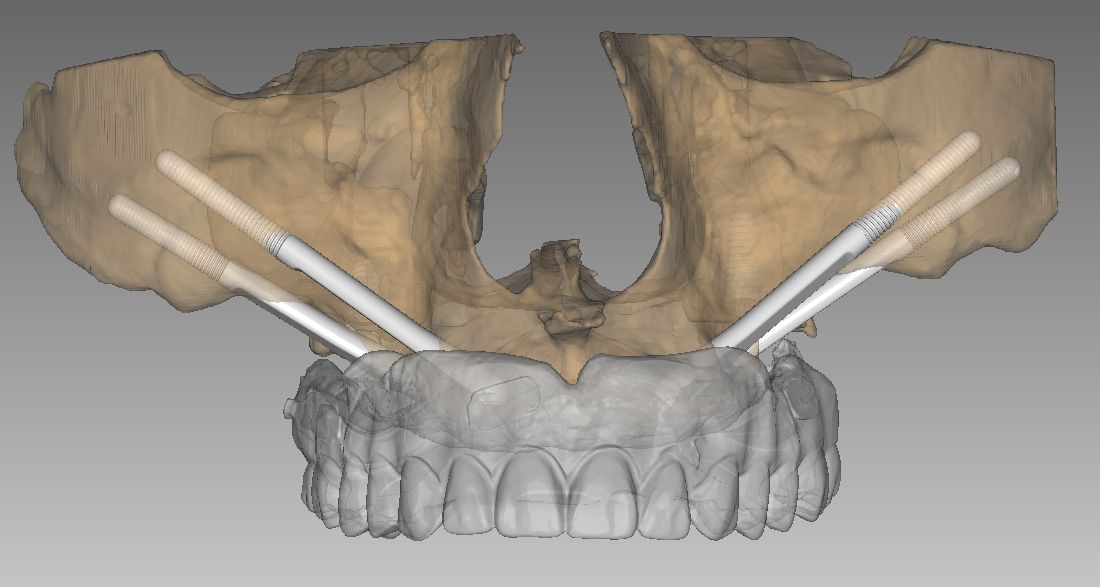

Cada paciente presenta una anatomía única. Por ello, en nuestra clínica de Soria, realizamos un estudio tridimensional para determinar qué combinación de implantes es la adecuada:

2. Implantes Pterigoideos

Se colocan en la parte más posterior del maxilar superior, anclándose en las apófisis pterigoides del hueso esfenoides. Son fundamentales para rehabilitar la zona de los molares (donde masticamos con más fuerza) sin necesidad de realizar elevaciones de seno maxilar. Aportan una estabilidad posterior crítica para la durabilidad de la prótesis.

La combinación de la visión prostodóncica y estética de la Dra. Aitziber Yagüe con la habilidad quirúrgica del Dr. Colmenero garantiza:

- Planificación digital y cirugía guiada para máxima precisión.